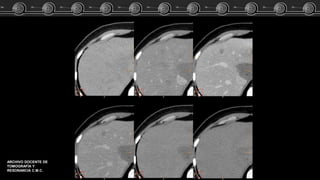

• Fase arterial: Captación

nodular periférica en fase

arterial, con captación lenta y

progresiva, centripeta e

isodensa respecto a los vasos.

• Fase venosa: Captación

progresiva, centripeta hasta el

relleno uniforme.

TC

• Simple: Isodensa o

hipointensa.

ARCHIVO DOCENTE DE

TOMOGRAFÍA Y

RESONANCIA C.M.C.

Hemangiomas Cavernosos • Fase arterial:Captación nodular periférica en fase arterial, con captación lenta y progresiva, centripeta e isodensa respecto a los vasos. • Fase venosa: Captación progresiva, centripeta hasta el relleno uniforme. TC • Simple: Isodensa o hipointensa.